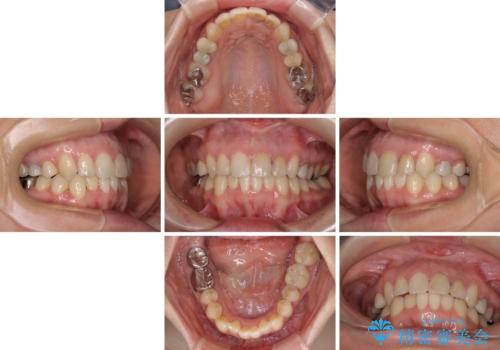

- 前歯のデコボコと奥歯の虫歯を気にして来院された患者様です。

主に下顎歯列全体の後方移動とIPR(歯と歯の間を削る)によってデコボコが解消するように設計し、インビザラインにより治療を行うこととしました。

矯正治療後半に下顎左右奥歯をセラミッククラウンにて補綴し、その後インビザラインによる歯列の仕上げを行うこととしました。

下顎前歯の叢生が速やかに改善されたため、1年3か月で治療を終えることができました。

下顎前歯は後戻りを起こしやすいため、舌側を細いワイヤーで固定することで後戻り対策を行っています。